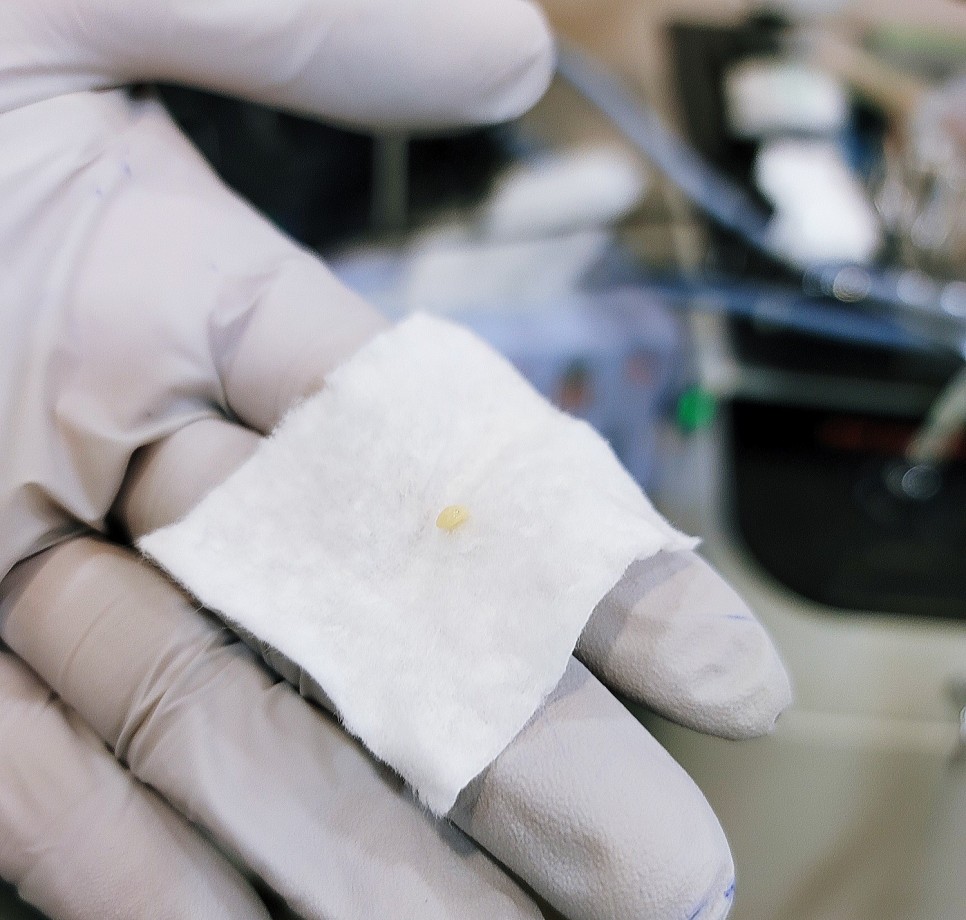

WoW…… 역시 예상대로 편도결석이 맞아서 의사고객님께서 흡입기(?)로 제거해주셨다.구역질이 나서 죽을뻔했다………눈물 또 흘립니다………지금보니 가끔 입안에서 저런 돌멩이?가 나오니까..내가 양치질을 안해서, 지금까지 먹은것중 하나인줄 알았는데..ㅋㅋㅋㅋㅋㅋㅋㅋㅋㅋㅋㅋㅋㅋㅋㅋㅋㅋㅋㅋㅋㅋㅋㅋㅋㅋㅋㅋㅋㅋㅋㅋ지금보니 그동안 편도결석이 저절로 떨어진것 같다.탱글탱글 이번에는 목의 붓기가 동시에 일어나 민감하게 받아들인 결과로 빨리 발견한 것 같습니다.